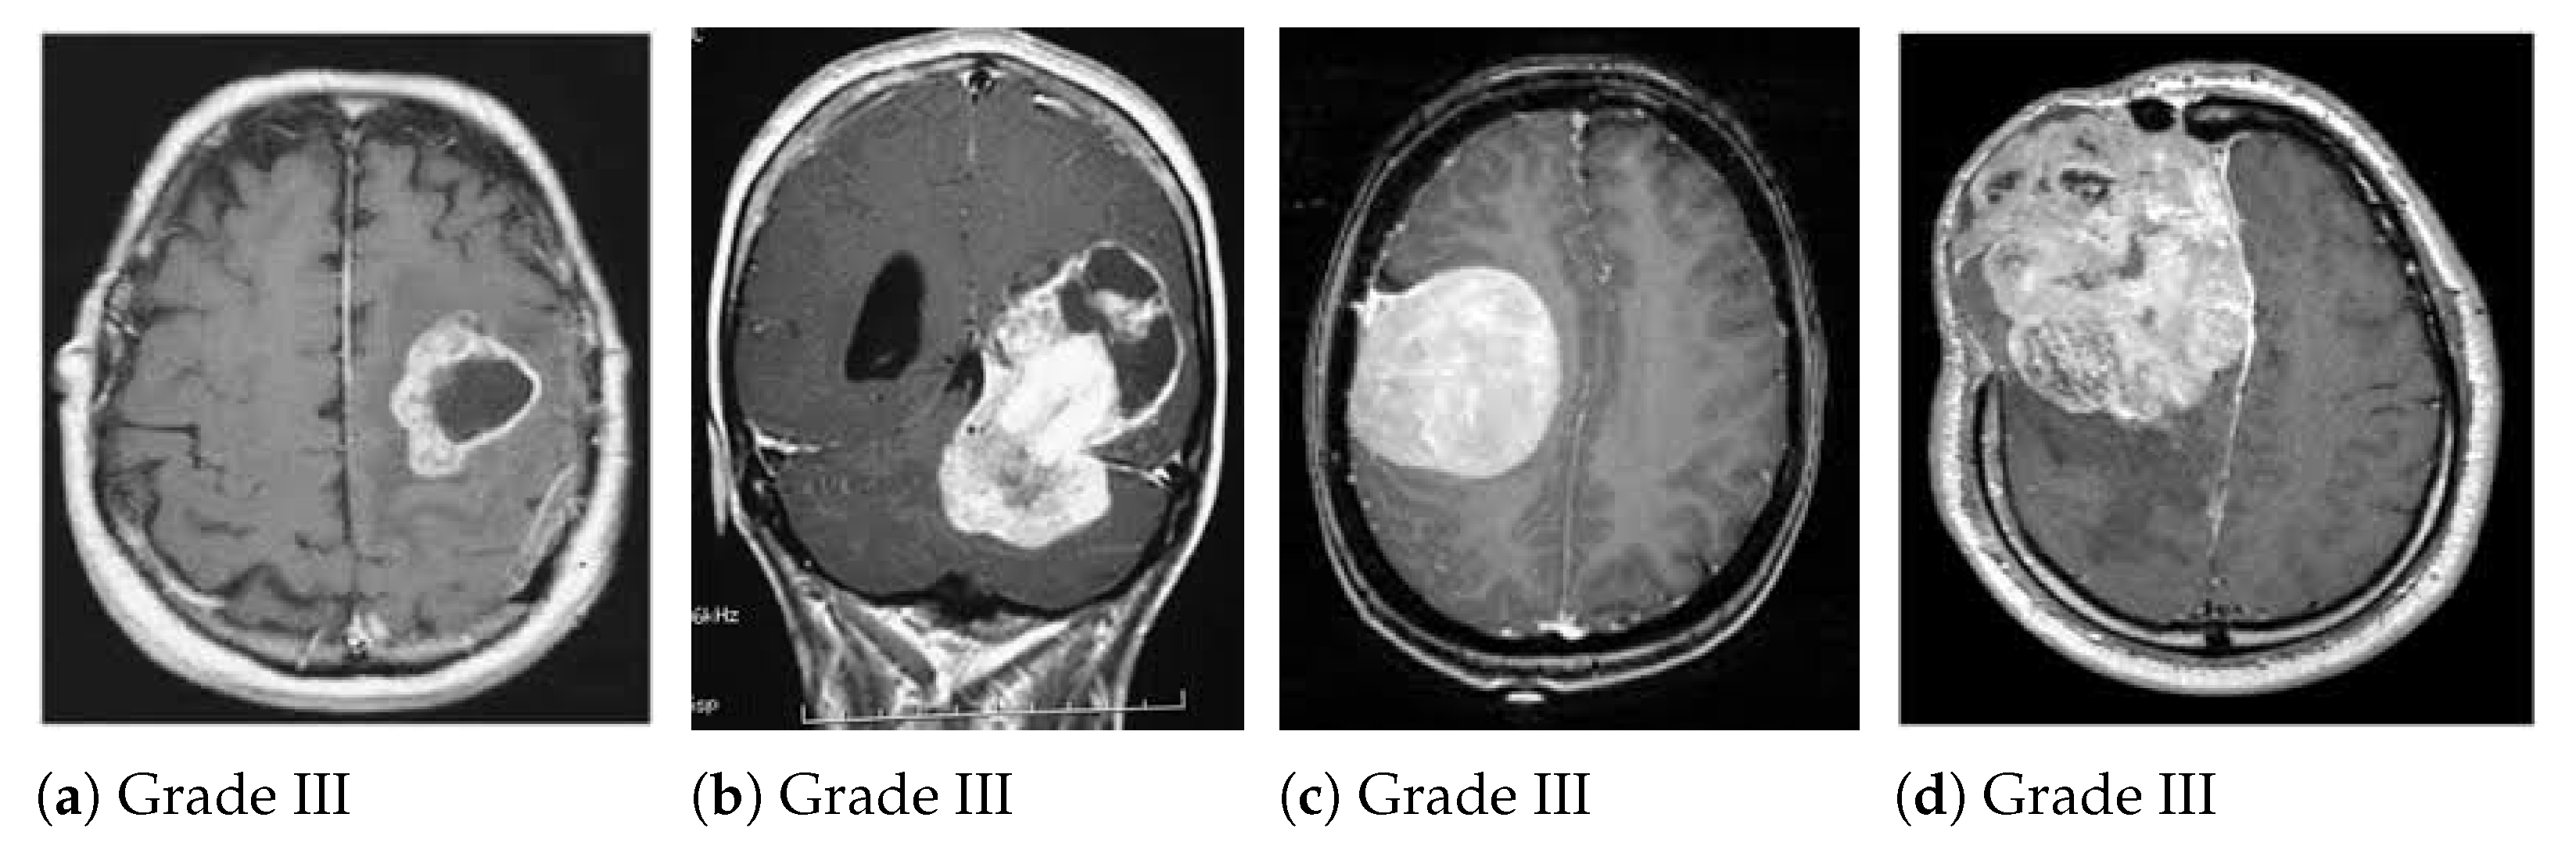

4.2. Dataset

5.2.1. BraTS 2018 Dataset Results

5.2.2. Figshare Dataset Results